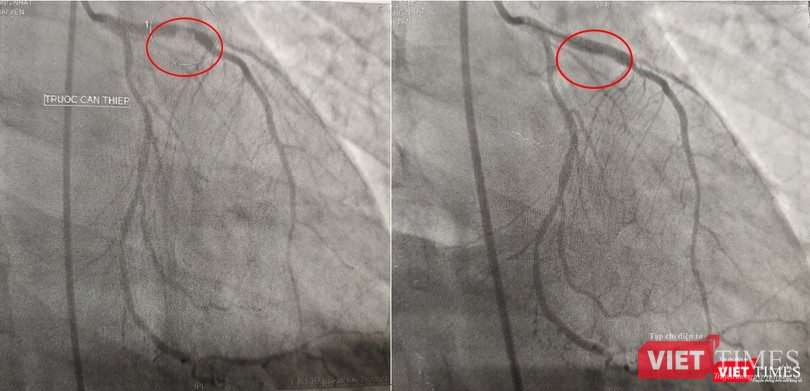

| Kết quả chụp DSA mạch vành: bán tắc đoạn gần LAD do huyết khối, can thiệp và đặt stent cho bệnh nhân |

Kết quả chụp mạch máu tại phòng DSA cho thấy bệnh nhân bị đột quỵ não do huyết khối gây ra tắc hoàn toàn một nhánh động mạch lớn của não, đồng thời, còn phát bệnh nhân bị bệnh cả 3 nhánh động mạch vành nặng với huyết khối gây tắc gần hoàn nhánh động mạch lớn nuôi trái tim LAD (nhánh động mạch liên thất trước), 2 nhánh còn lại có một nhánh hẹp nặng, một nhánh bị tắc hoàn toàn mạn tính đã lâu.